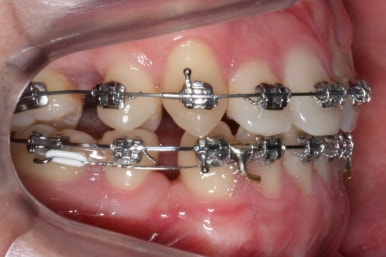

위아랫니가 각각 가지런해지고 있는 것을 볼 수 있습니다.

적절한 시기가 되면 악궁확장장치를 제거하고, 확장장치가 걸려있던 치아도 가지런하게 해줍니다.

윗니는 아직 가지런하게 하는 작업 중이며, 아랫니는 가지런하게 하는 작업은 거의 다 되었습니다.

이제 아랫니는 이 뽑은 자리를 앞뒤로 당겨서 없애주어야 합니다. 보통은 앞니가 뒤로 많이 들어오기 때문에 이번 환자분 처럼 앞니가 거꾸로 물리는 경우 앞니를 제대로 물리게 해줄 수 있습니다.

계속 윗니는 가지런히 해주고 있으며 아랫니는 앞뒤를 뒤로 당기고 있습니다.

거꾸로 물리던 앞니가 서서히 개선되어 가는 것을 볼 수 있습니다.